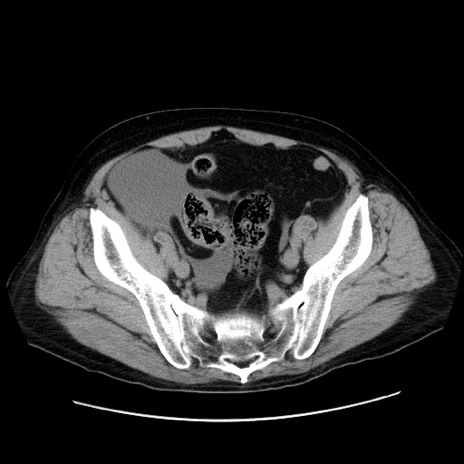

症例30(横断像)

【症例】80歳代男性

【主訴】臍周囲痛

【現病歴】約6時間前から臍下部痛が出現。次第に腹部膨隆・背部痛も生じてきたため来院。背部痛の場所は変化しない。

【身体所見】意識清明、BT 36.3℃、BP  131/87mmHg、P 87bpm、SpO2 100%(RA)、臍周囲自発痛・圧痛あり、反跳痛なし、自発痛部位に一致して板状硬あり、腹部膨隆、腸雑音減弱、CVA tenderness両側陰性。

【データ】WBC 19600、CRP 0.33